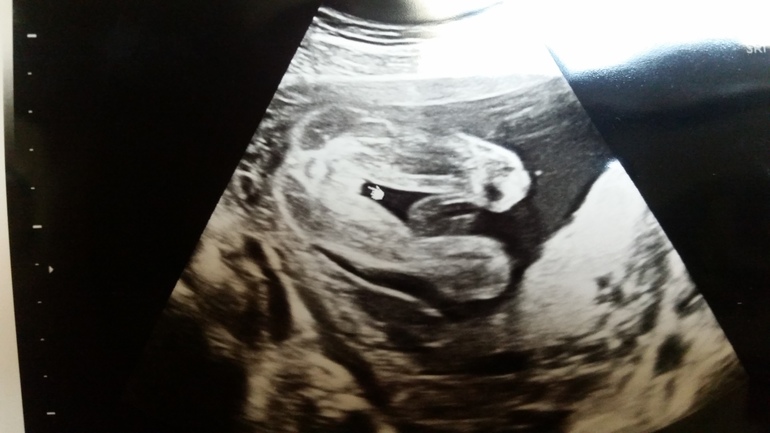

ДЕВОЧКА!! Я аж с кушетки чуть не упала)) Неожиданно очень. Уж я себя оочень усиленно на парня настроила, даже шмотки от племянника приняла. Но нет, все же шопингу быть 🤗 Лежала, все переспрашивала, сомневалась, а вдруг писюн где-нить за ногой спрятался)) врач поржал и крупным планом мне показал на мониторе "половую щель"))

Единственное, барышня отвернулась спиной не смогли сердце осмотреть как положено, поэтому повторно через пару недель придется еще раз прийти. А так все в порядке, плацента поднялась, размеры милипуськи соответствуют сроку. Ноги косолапые, как и у Вани. Папаша наш и девочку не пощадил, всем передает свои ножки-ласты по наследству.

408 грамм женского счастья, вид снизу: